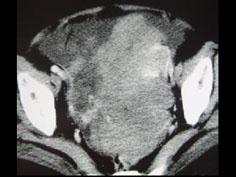

问题 50岁女性患者,消瘦乏力一年余,来院就诊,B超提示盆腔巨大包块,行CT检查如图所示,你认为最可能的答案是 ( )

选项 A、卵巢粘液瘤 B、卵巢皮样囊肿 C、卵巢囊肿 D、卵巢异位妊娠 E、卵巢癌

答案 E